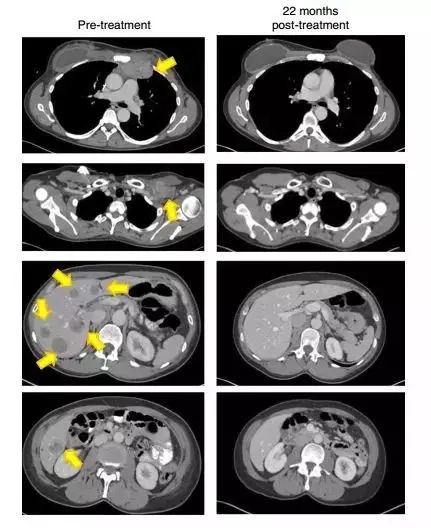

当900亿个免疫细胞被输入患者体内后,奇迹出现了。6个月后,患者的肿瘤突变负荷锐减一半。22个月后,借助影像学观察,所有肿瘤都消失了!

▲22个月后,这名患者的肿瘤(黄色箭头)消失得无影无踪(图片来源:《Nature Medicine》)